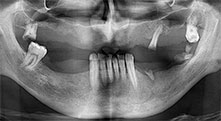

For what indications do you use the saws?

Bratu: We routinely use the instruments for harvesting bone blocks and splitting alveolar ridges. We also use the Piezomed B6/B7 for osteotomy of impacted teeth and removing failed implants. All indications that require deep, clean cuts.

Bratu: I consider piezo surgery a great leap forward in oral surgery. The technique makes bone preparation safer and easier. Little bone is lost, for example in extractions. This is very important in the aesthetic zone, particularly if immediate implantation is planned. Piezo surgery is also safer for soft tissue: injuries to membranes in the sinus are basically history, as are nerve injuries when bone blocks are being harvested. Data indicating reduced postoperative swelling and pain are also available. Piezo surgery is also ideal for preparation of sinus septa. And last but not least, our patients benefit from the atraumatic nature of this technology.